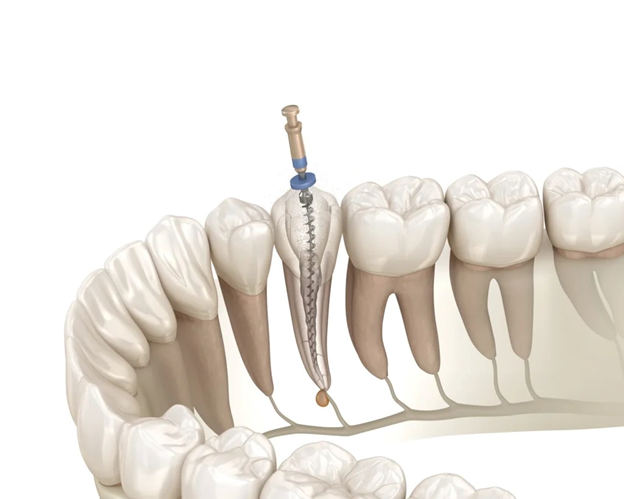

Bước 4: Điều trị tủy răng chính xác – bảo tồn tối đa

Bác sĩ nhẹ nhàng mở đường tiếp cận ống tủy, sau đó:

- Loại bỏ hoàn toàn phần tủy viêm hoặc hoại tử

- Làm sạch – tạo hình – khử trùng hệ thống ống tủy

- Đảm bảo loại bỏ triệt để vi khuẩn gây viêm nhiễm

Quy trình được thực hiện tỉ mỉ, giúp giữ lại mô răng khỏe mạnh tối đa.

Bước 5: Trám bít ống tủy & phục hồi răng thẩm mỹ

Sau khi điều trị tủy hoàn tất, bác sĩ:

- Trám bít kín ống tủy bằng vật liệu sinh học chuyên dụng

- Ngăn tái nhiễm vi khuẩn